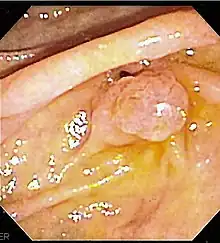

The major duodenal papilla, seen on duodenoscopy at the time of ERCP. This is the protrusion of the ampulla of Vater into the duodenum. | |

The ampulla of Vater, hepatopancreatic ampulla or hepatopancreatic duct is the common duct that is usually formed by a union of the common bile duct and the pancreatic duct within the wall of the duodenum. This common duct usually features a dilation ("ampulla"). The common duct then opens medially into the descending part of the duodenum at the major duodenal papilla. The common duct usually measures 2-10mm in length.[1]

The ampulla of Vater is an important landmark halfway along the second part of the duodenum marking the transition from foregut to midgut.